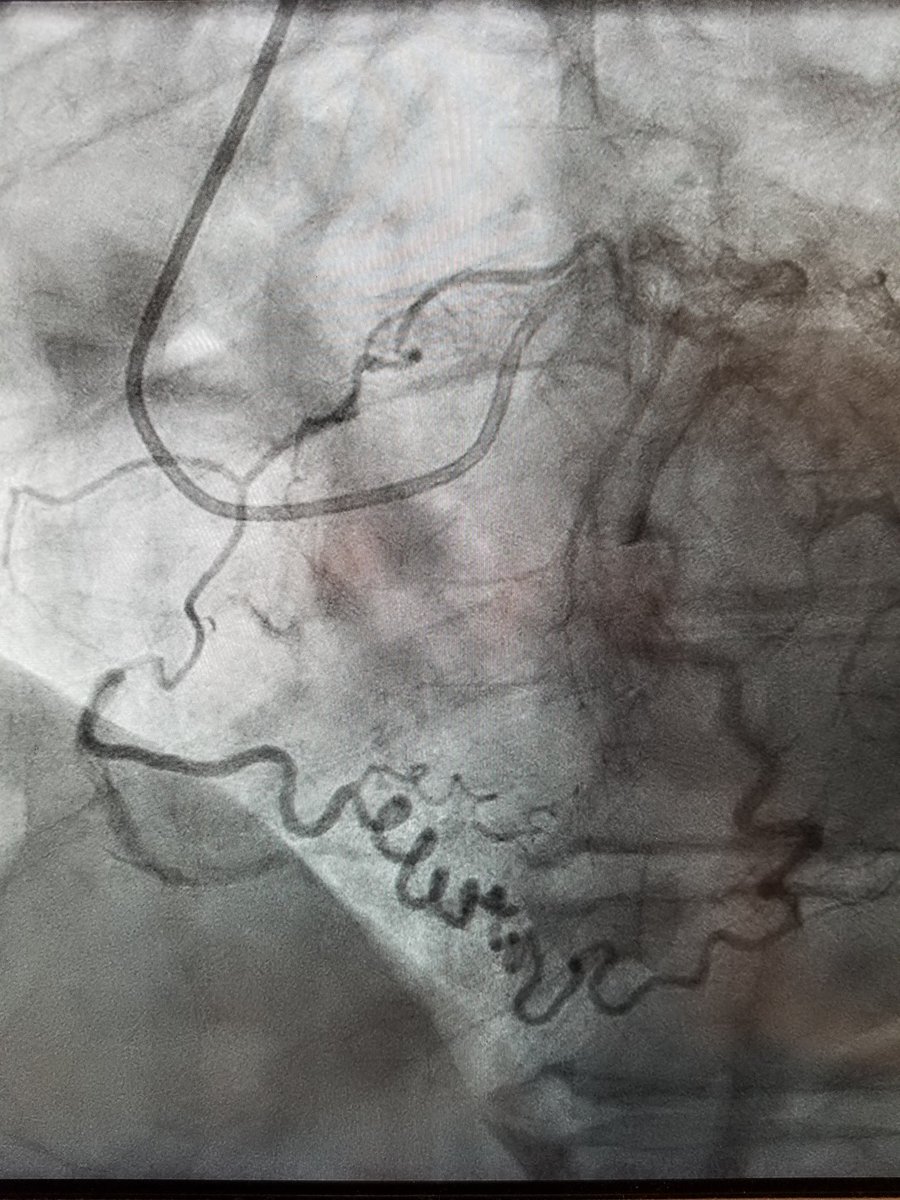

"Would you switch to retrograde for this near flush occluded RCA #CTO101 if needed? No septals. Large tortuous LAD epicardial. If so, microcatheter of choice? @evandrofilhobr @perc_surgeon @DrAmirKaki @Babar_Basir @KAlaswadMD @Retrograde_CTO"